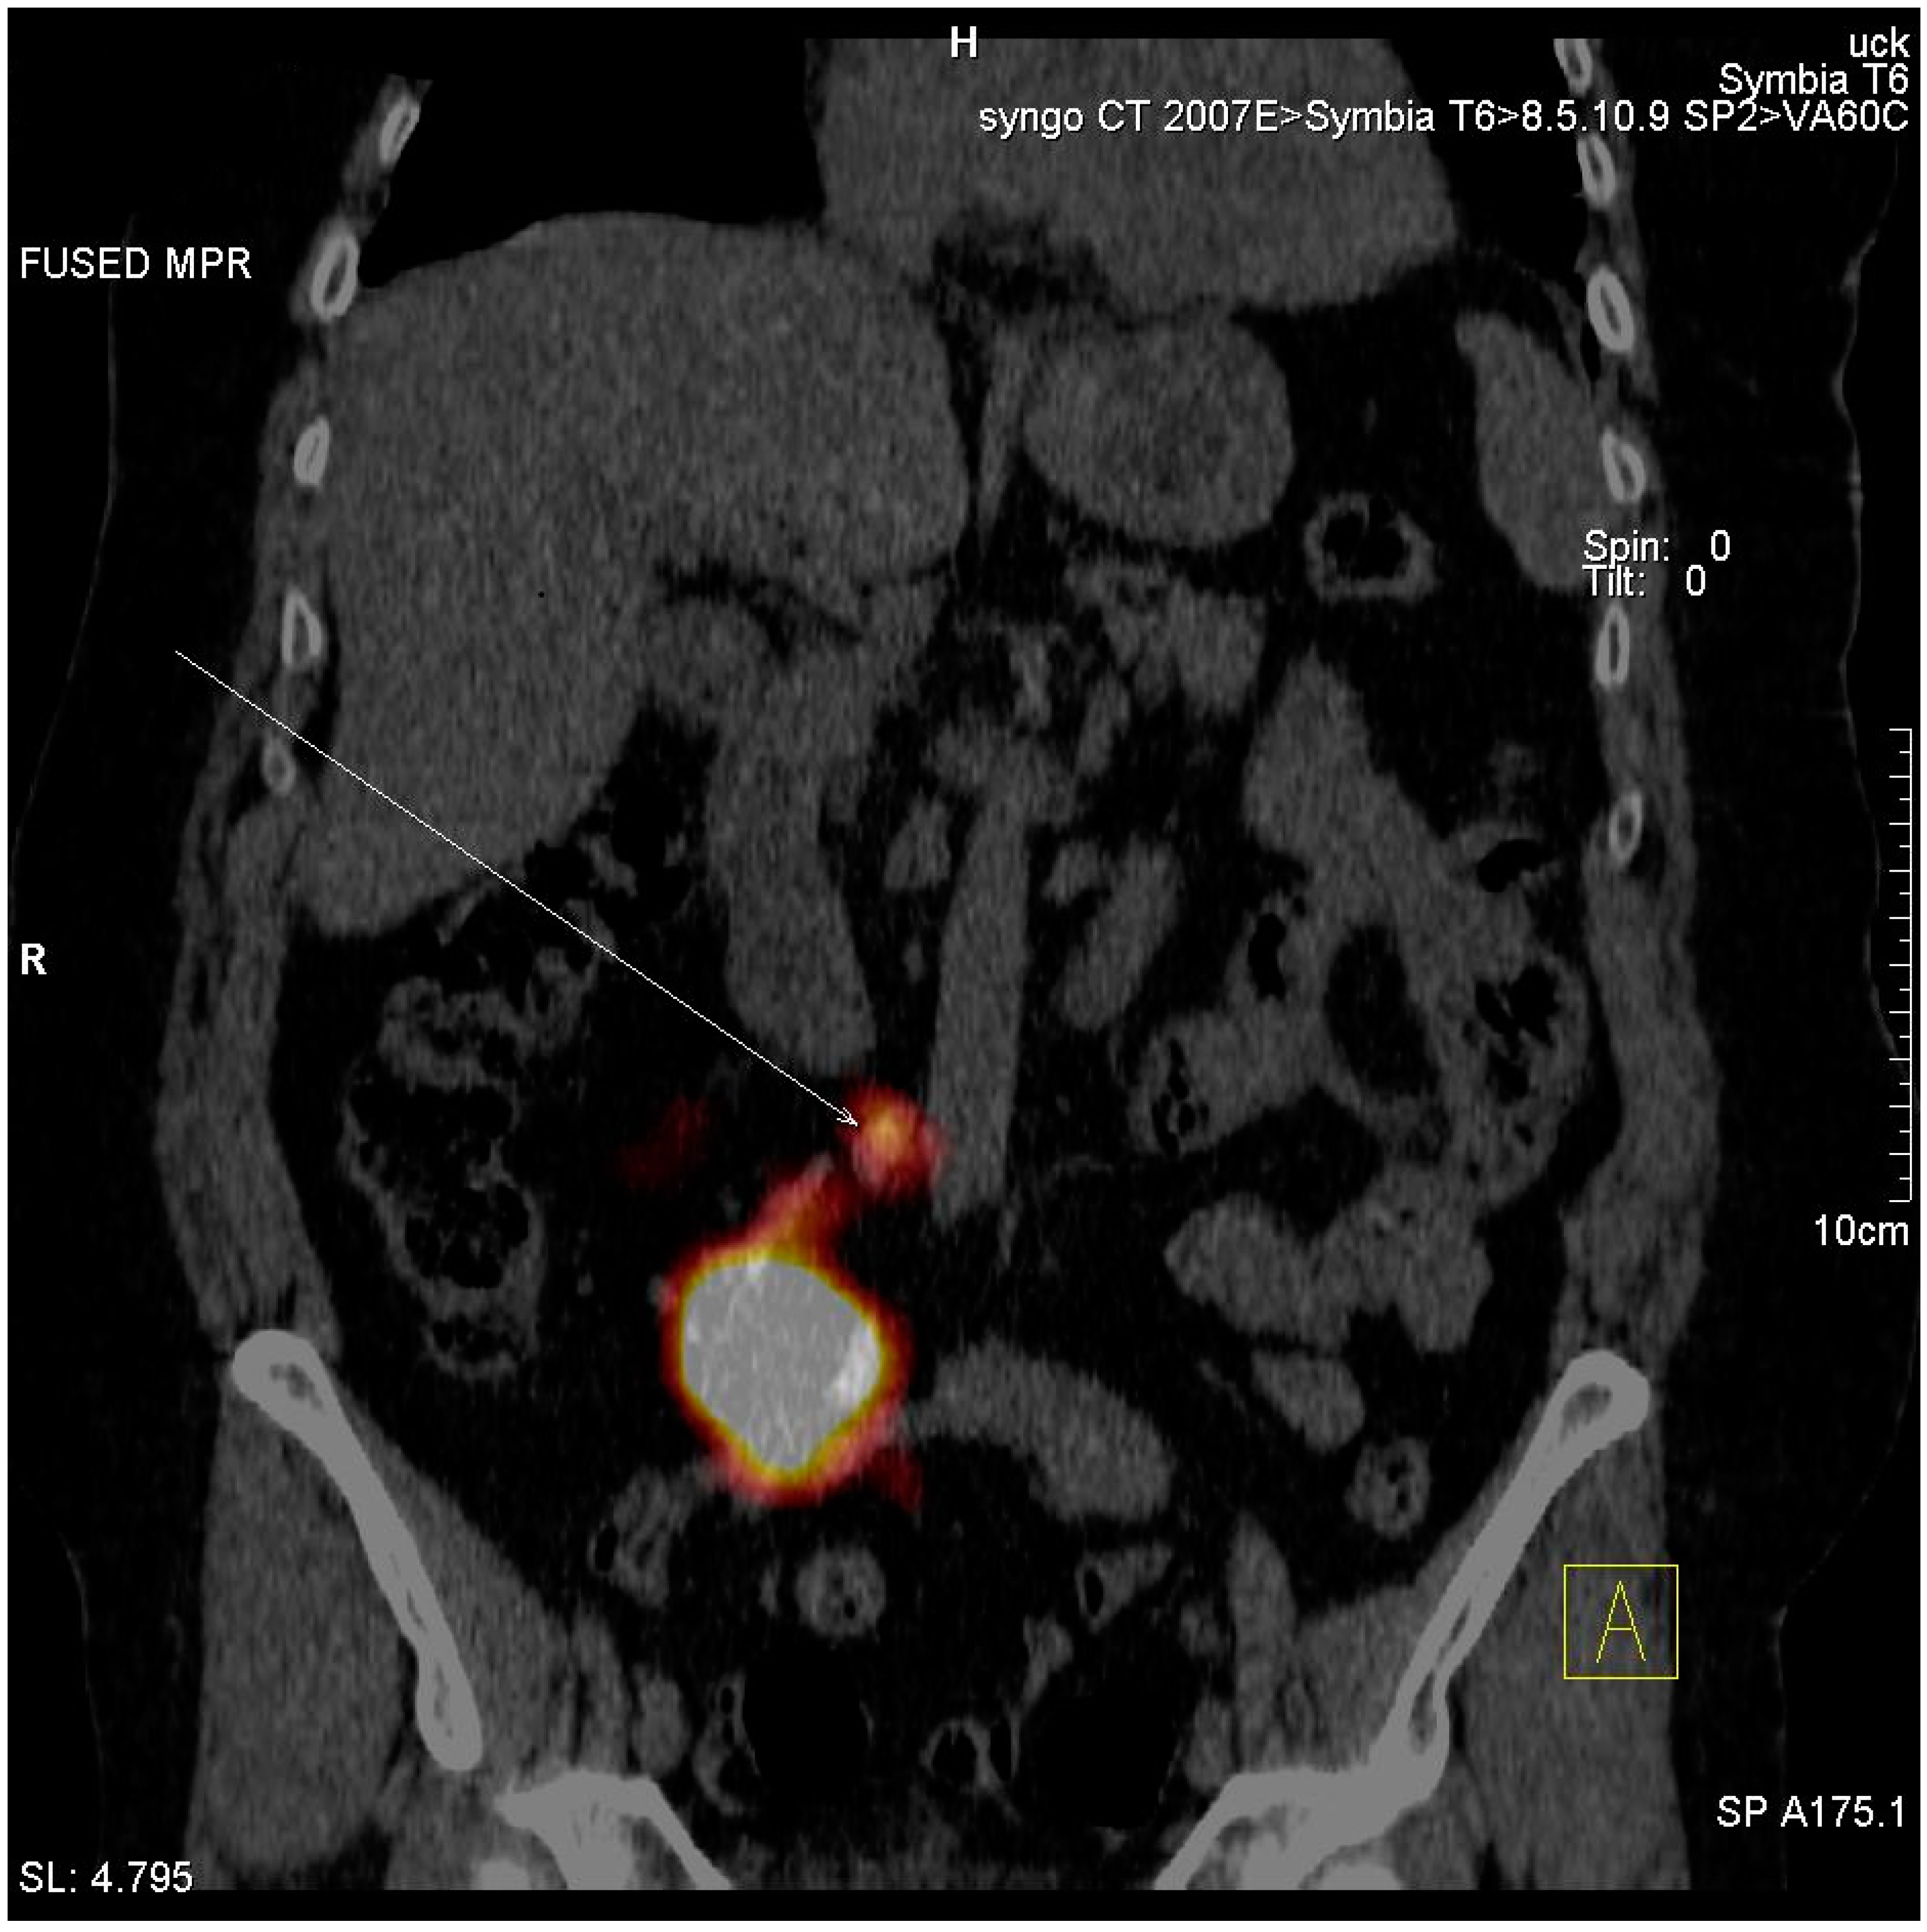

| Lymphatic outflow analysis | |

| Number of patients with identified SLNs | 2 (10.5%) |

| Number of patients with no lymphatic outflow | 17 (89.5%) |

| Number of identified SLNs | 2 (10.5%) |